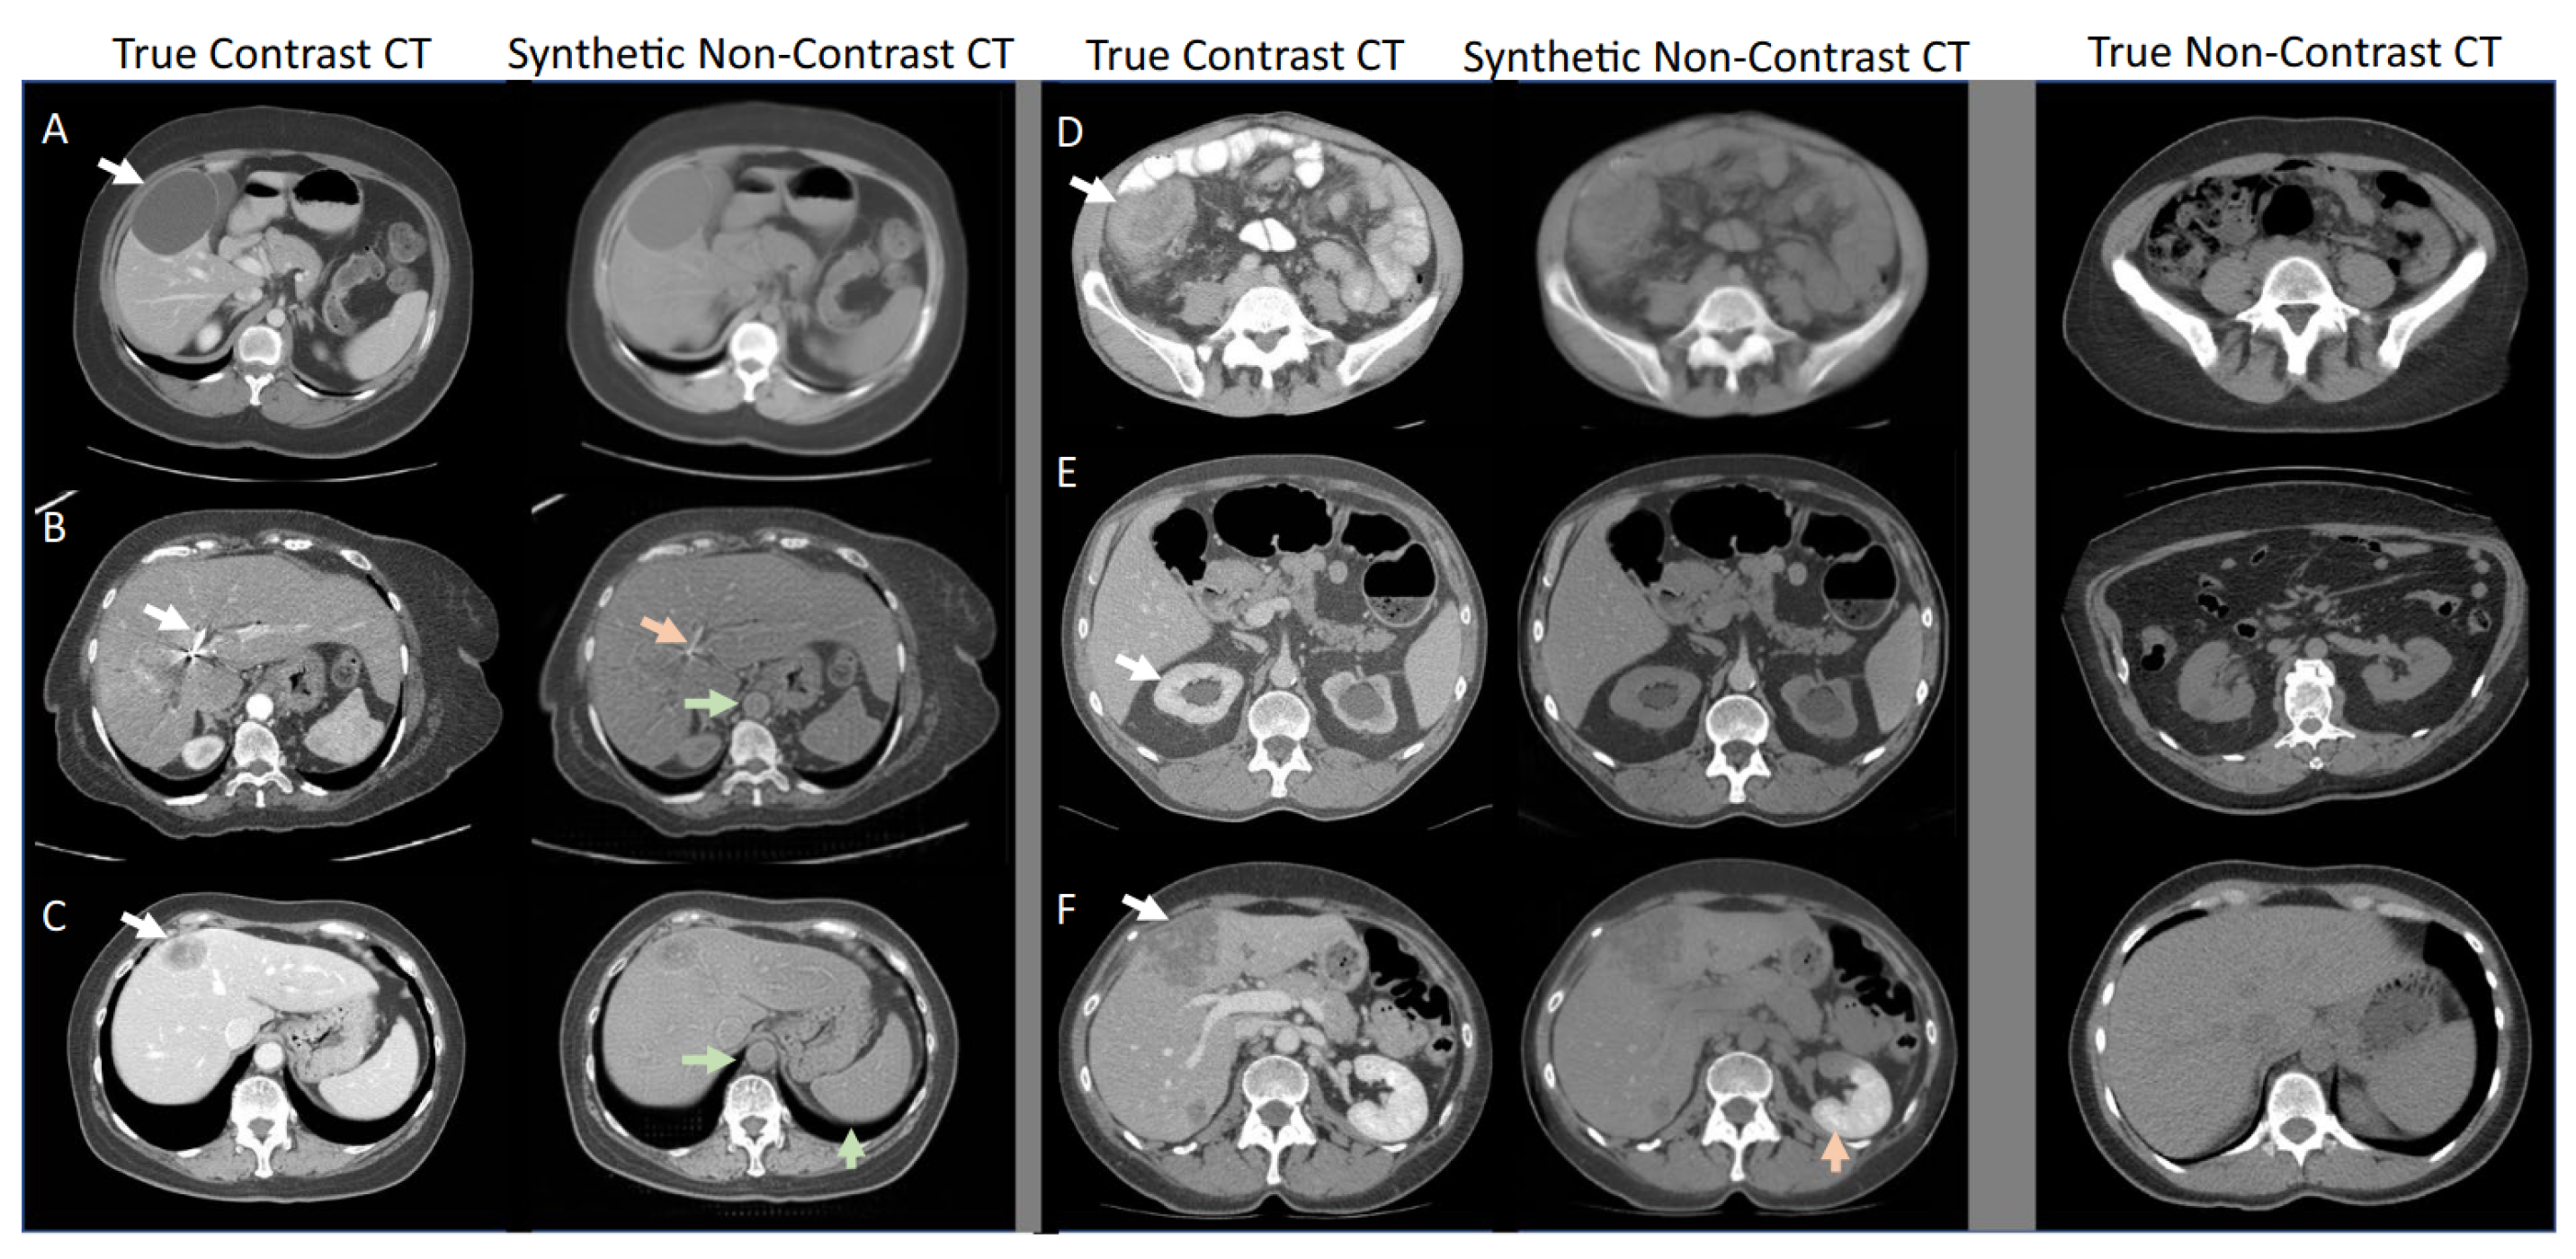

Consider the process of labelling medical images. A technical team might mark basic visual features, but a radiologist knows that a slight shadow could be meaningless in one context and critical in another.